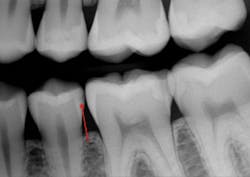

Additional clinical time for dentists: A small Class II resin-based composite can usually be placed in a short time, while larger composites require much more time and expertise (figure 3). Third-party payers pay the same regardless of the size of the restoration. If lesions are not identified early, the dentist must spend more time preparing the tooth and then placing and finishing the restoration. Not only does the patient suffer shorter restoration longevity, additional future replacement of the restoration, and higher cost, but the dentist also expends more time and effort for a large restoration and receives less proportionate revenue for the services (figures 4a and 4b).

Figure 3: Note the presence of a lesion on the distal surface of the mandibular second premolar, which appears to be about halfway through the enamel. Most current digital radiographs show only about half of the actual depth of initial caries as shown in the partly finished prep. The lesion was already into the dentin about 1 mm as shown on this partially completed tooth preparation.

Figures 4a and 4b: The restored premolar tooth is the same premolar shown in Figure 3. Such small restorations serve far longer than large ones as shown in the molar.